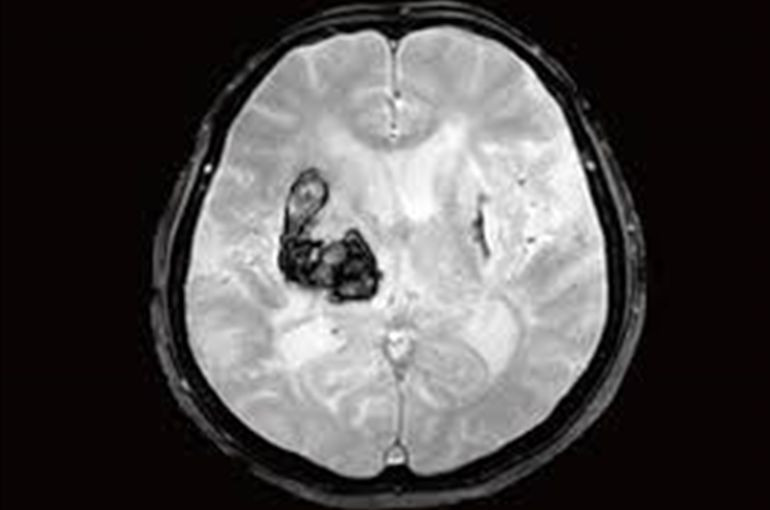

□脳出血

脳出血が起きた時も頭痛が出ます。

脳出血時の頭痛の特徴としては、

・手足にしびれが生じ、感覚に鈍くなる。

・意識がぼんやりし、ろれつが回らなくなる

といった特徴があります。

そういったケースの場合、整体では改善しないのすぐ病院に行ってください。